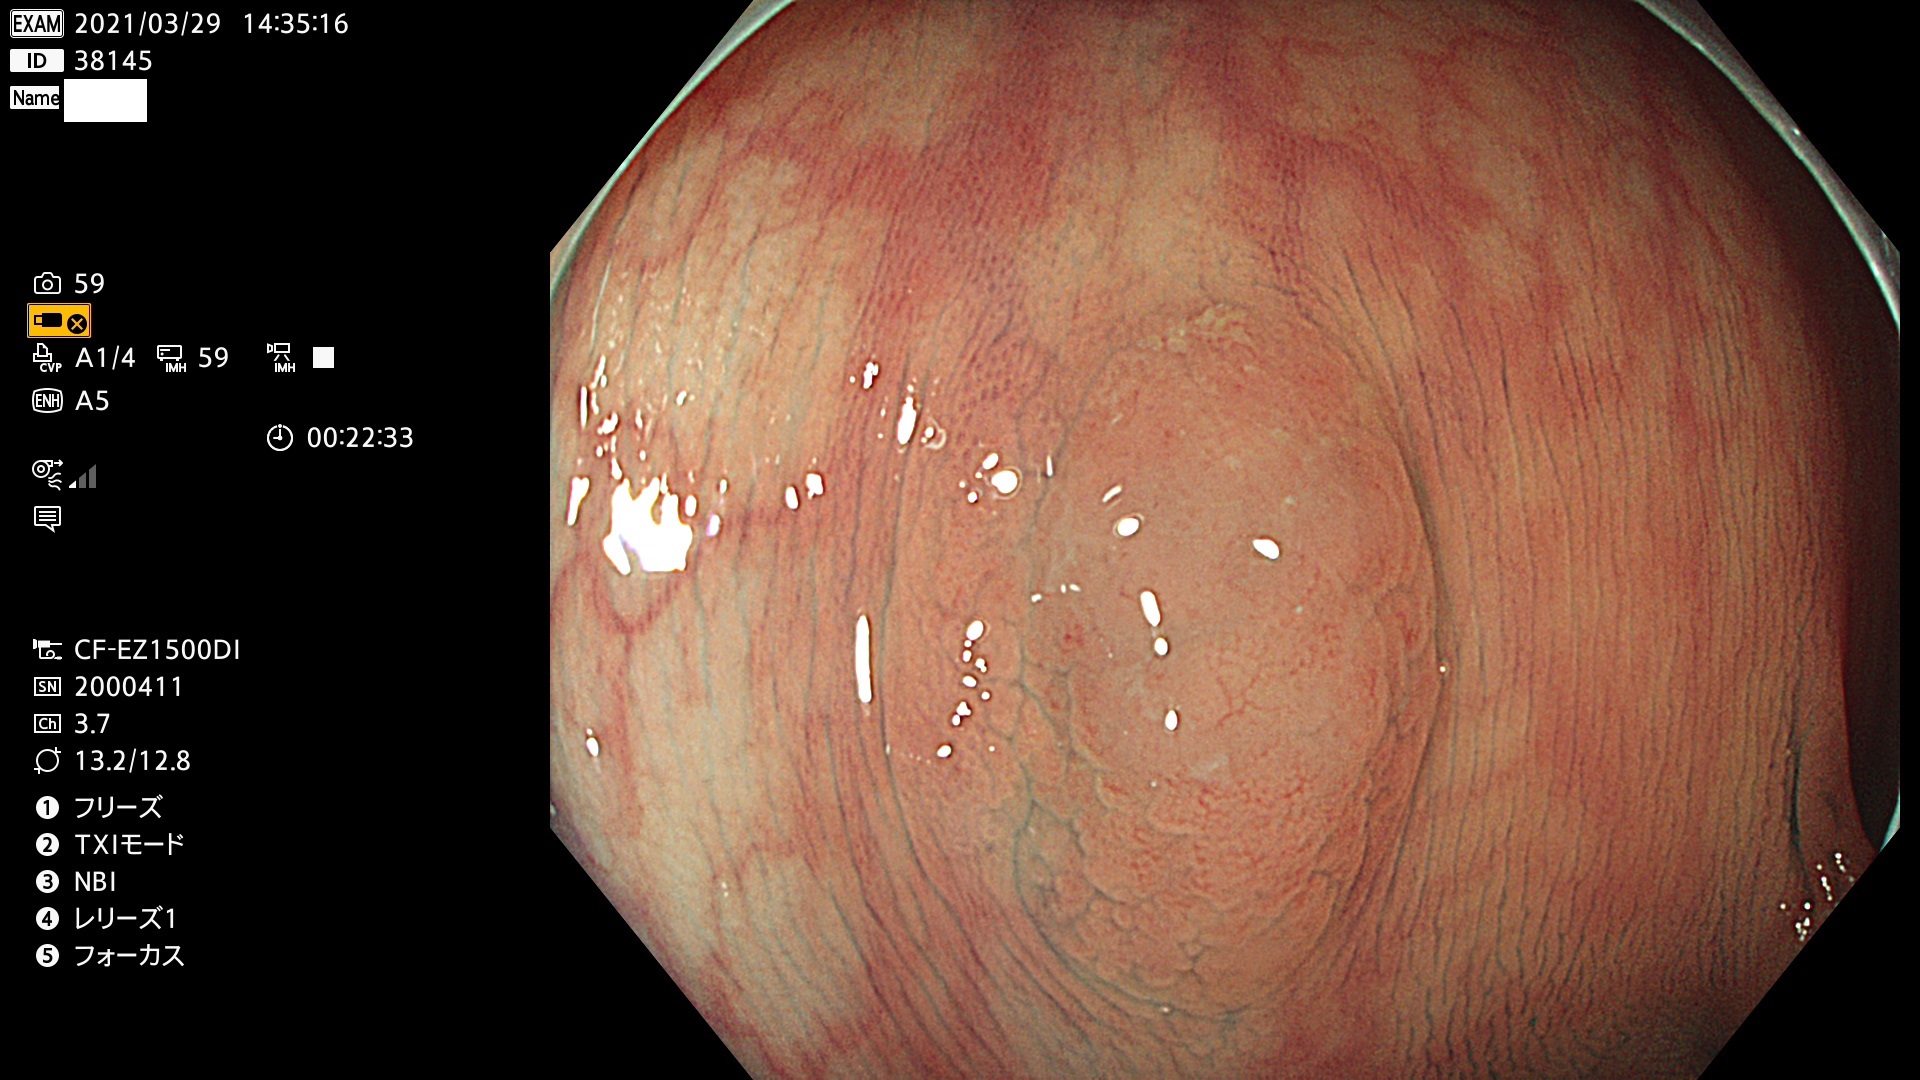

発見困難で危険性の高い平坦型病変(上記100名より抽出) ![]()